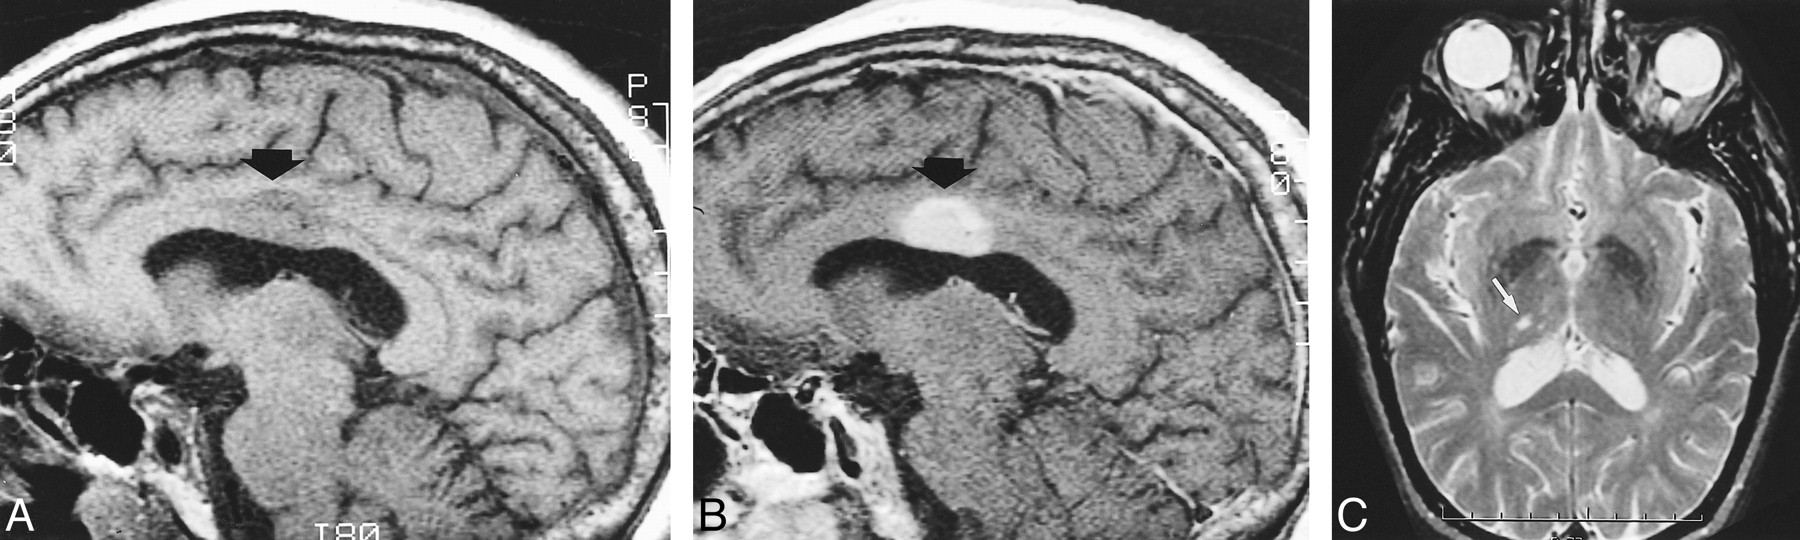

A 67-year-old man, with past medical history significant for hypertension, developed sudden-onset vertigo and left-leg paresthesia. His vertigo resolved, but his left-sided weakness persisted. An initial non-contrast CT performed upon admission showed a subtle region of low attenuation in the body of the corpus callosum on the right side. Long-TR MR imaging, performed 10 days after initial CT, depicted an ovoid hyperintense lesion within the body of the right corpus callosum that was hypointense on the T1-weighted images and enhanced homogeneously (Fig 3A and B). There was mild mass effect on the roof of the lateral ventricle. The patient's symptoms were attributed to a small infarct within the right thalamus (Fig 3C). The corpus callosum lesion was considered to be an asymptomatic tumor and a biopsy was performed 2 weeks after admission. The results of the biopsy confirmed an infarct.

Case 3. Sagittal precontrast T1-weighted image (A) (400/12/2) shows a hypointense ovoid mass (arrow) within the body of the corpus callosum, depressing the roof of the lateral ventricle. After administration of contrast material (B) (400/12/2), it enhances homogeneously. A small infarct (white arrow) is noted within the right thalamus on the axial T2-weighted image (C) (2560/90/1). Subsequent biopsy confirmed an infarct